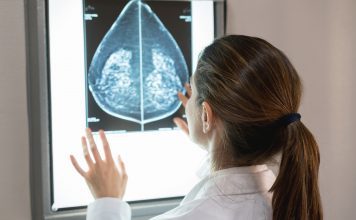

Defence is focused on developing dendritic cell-based cancer vaccines, ADCs, and small super-antagonist molecules capable of targeting various cancer indications (lymphoma, melanoma, colon, and breast cancer) as well as infectious diseases (COVID-19, HPV, and more).